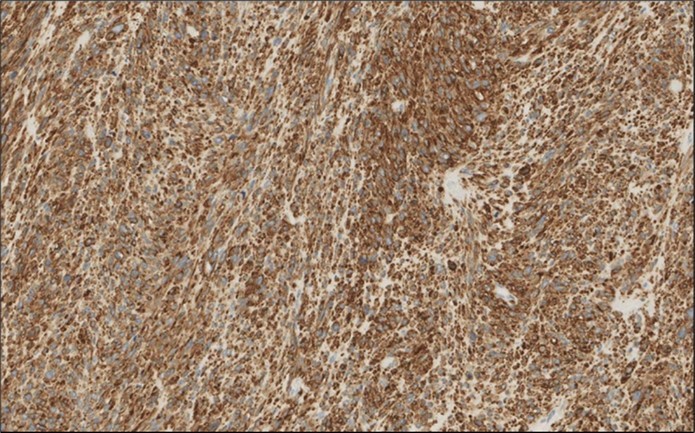

Figure 4.Left thyroid Cells are diffusely positive for Caldesmon immunohistochemistry (IHC, x200)

cancer, or other metastatic tumors without further testing with genetic or molecular studies 3, 7. Immunohistochemical testing plays a vital role in differentiating LMS from such similar tumors as it stains positive for vimentin and smooth muscle actin (SMA), and is variably positive for HHF35, desmin (50%-100%), and H-caldesmon 3, 6. Moreover, there were no reported cases where thyroid LMS stained positive for thyroglobulin, cytokeratin, calcitonin, chromogranin, or protein S100 3. Our patient’s left thyroid biopsy showed the characteristic microscopic features and was positive for SMA, desmin, caldesmon, P63 with patchy EMA (Figure 1, Figure 2, Figure 3, Figure 4) as well as her liver biopsy (Figure 5, Figure 6, Figure 7); whereas her right thyroid showed clear papillary thyroid cancer cell features (Figure 8, Figure 9).